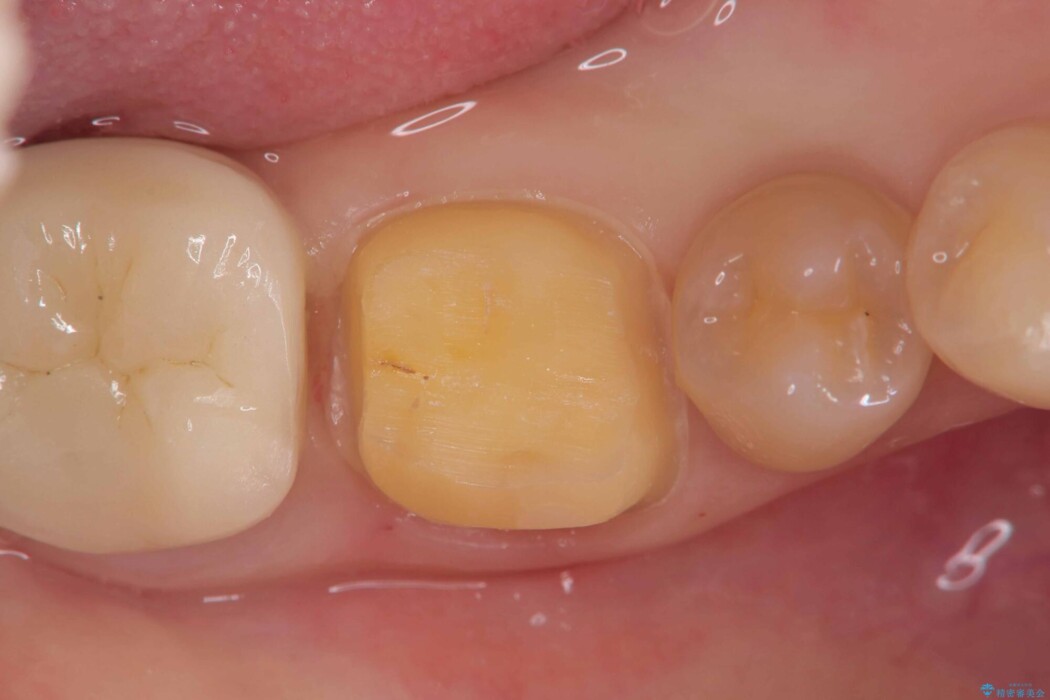

歯と歯の間に虫歯があった患者様です。

噛む面や外側にも過去の詰め物が入っている状態で、このように詰め物の範囲が大きいと治療後に歯が割れてしまうリスクが高くなります。

今回は歯の強度と将来的な破折リスクを考慮し、セラミッククラウンによる治療を行うこととしました。